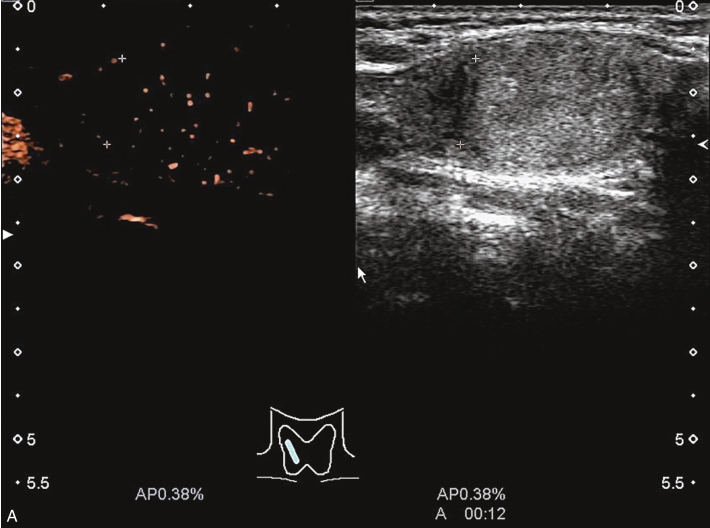

甲状腺囊肿常规超声表现为边界清晰、形态较规则的无回声结节,内可见点状强回声,后伴“彗星尾”征,CDFI内部无明显血流信号,见图1-3-1。

图1-3-1 甲状腺囊肿常规超声声像图

A.甲状腺左叶纵切面;B.CDFI血流图